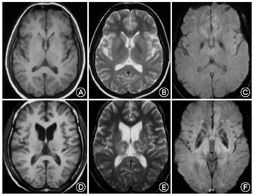

2例有神经症状的WD携带者,SWI苍白球、壳核、丘脑有稍低信号。其余WD携带者脑部MRI及SWI未发现异常(图1)。

有症状的WD携带者丘脑、苍白球、壳核SWI相位值(CP值)较健康对照降低,但差异无统计学意义。有症状WD携带者黑质、尾状核、壳核部位CP值高于WD患者(P=0.032,0.028,0.029),无症状WD携带者黑质、丘脑、尾状核、苍白球、壳核CP值高于WD患者(P=0.044,0.039,0.043,0.020,0.031)(表3)。